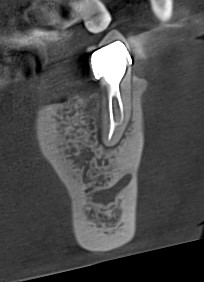

- Consultație și diagnostic precis (radiografie digitală sau tomografie CBCT)

- Utilizarea microscopului endodontic pentru vizibilitate maximă